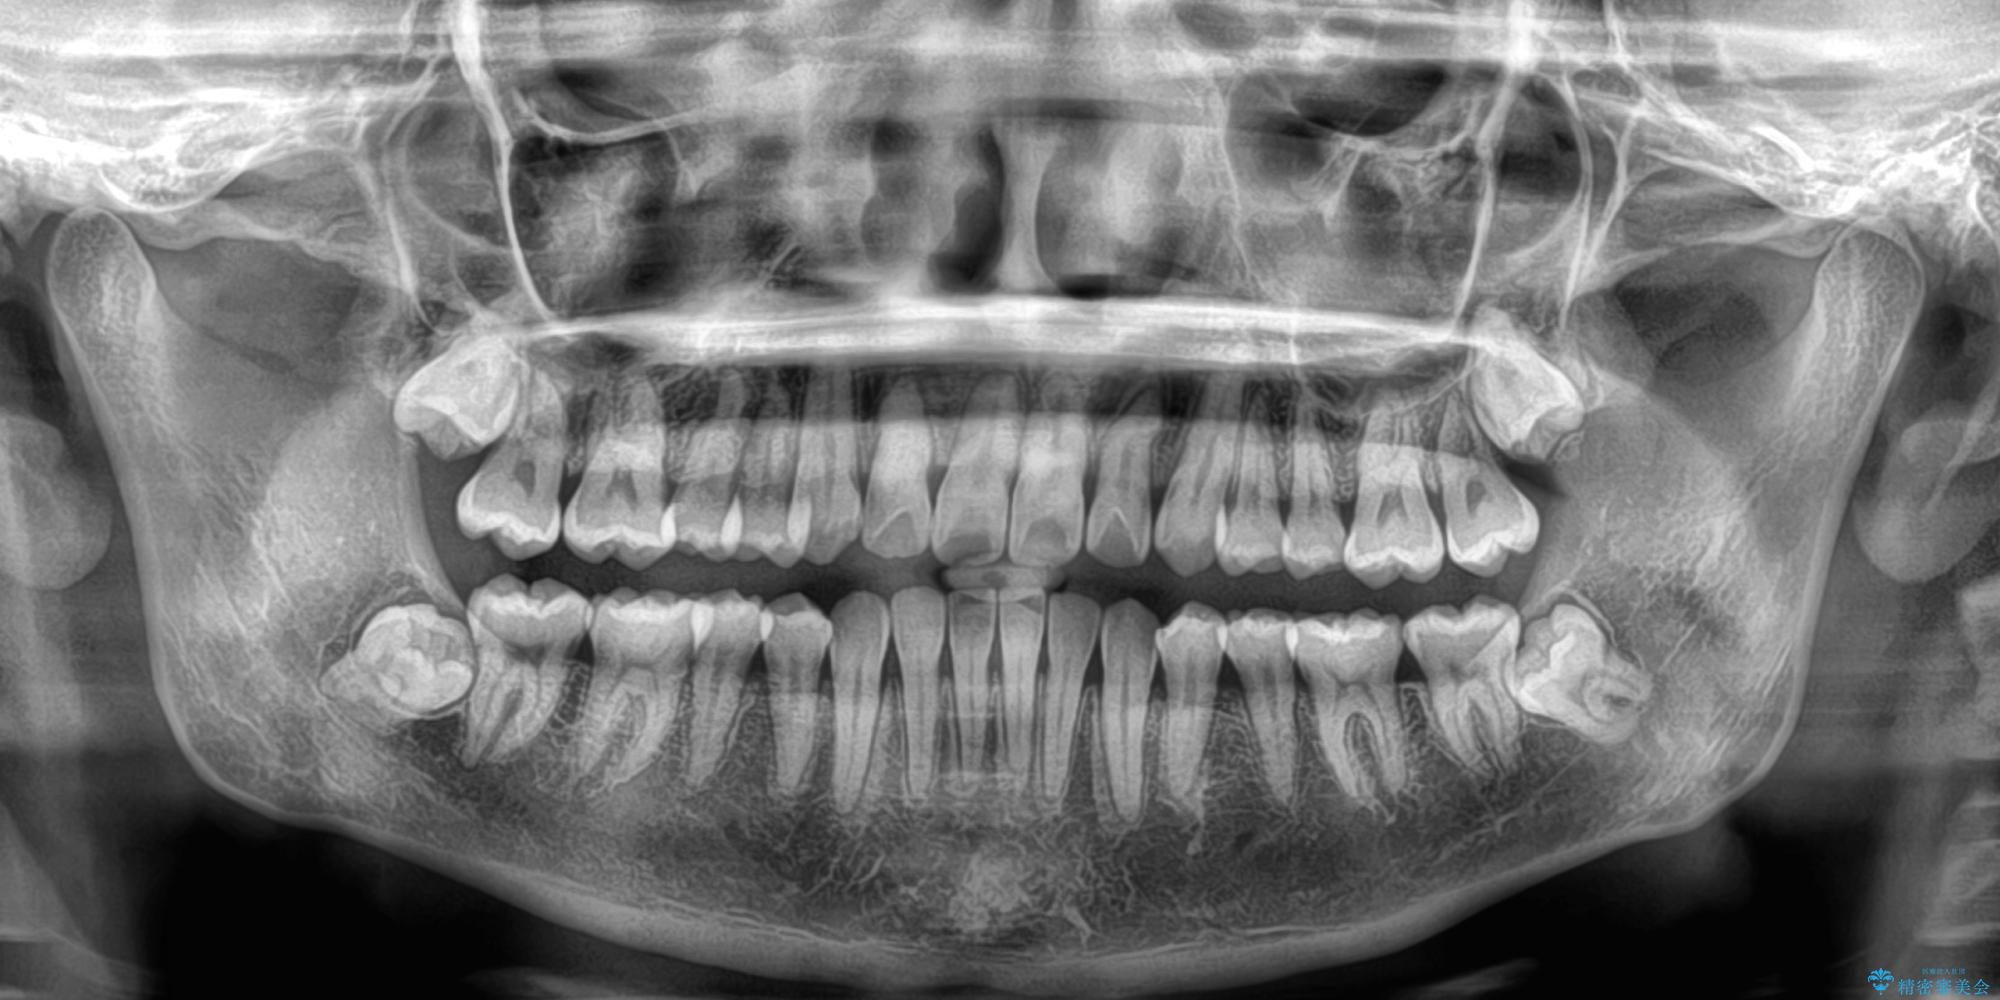

- 上顎前歯のクロスバイトを気にして来院された患者様です。

ワイヤー矯正でもマウスピース矯正でも対応可能でしたが、マウスピースによる自己管理に一切の自信がないとのことで、ワイヤー装置にて矯正治療を行うこととしました。

- 症状により、抜歯が必要な場合があります